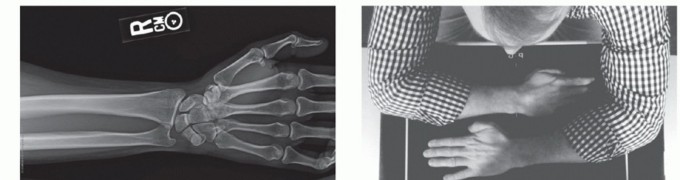

If the examination reveals wrist or forearm tenderness, the examiner should have a low threshold for obtaining bilateral wrist posteroanterior (PA) views to rule out an Essex-Lopresti lesion. Alternatively, this can be done with a one cassette view to minimize radiation exposure (FIG 9).

FIG 9 • A. A positive Itamura simultaneous DRUJ view showing negative ulnar variance of the uninjured left DRUJ compared with neutral ulnar variance of the right injured DRUJ suggesting interosseous membrane disruption. Patient had a right radial head fracture and proximal migration of the radius respective to the ulna (Essex-Lopresti fracture). B. Image is taken with 90-degree shoulder flexion, 90-degree elbow flexion, and 90-degree forearm pronation.